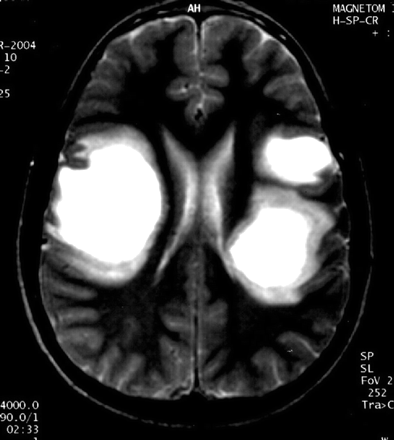

提出了四种模式的大脑参与描述ADEM的磁共振成像结果21:1)ADEM小病变(少于5毫米;图1);2)ADEM大支流,块状病变,簇状或频繁广泛perilesional水肿和质量效应(图2);3)ADEM附加对称bithalamic参与(图3);和4)急性出血性脑脊髓炎(咳咳),当一些出血的证据可以确定大脱髓鞘病变(图4)。核磁共振成像模式似乎并不与任何特定的结果或残疾,作为大型儿童群体中观察到,21因为大多数病变往往解决后续成像研究。21日,32然而,这种分类可能是有用的在考虑的鉴别诊断ADEM和可能有助于识别那些孩子来说,初始ADEM-phenotype真的是第一个女士的表现。

图4。急性出血性脑脊髓炎。(A)轴向t2加权MRI与著名的双边hyperintense病变区域的信号很低,相应的血红蛋白的分解产物,在一个5个月大的孩子男孩,百日咳疫苗接种后2周。(B)轴向t1加权磁共振成像相同的情况下,显示自发hyperintense大hypointense内病变的信号。